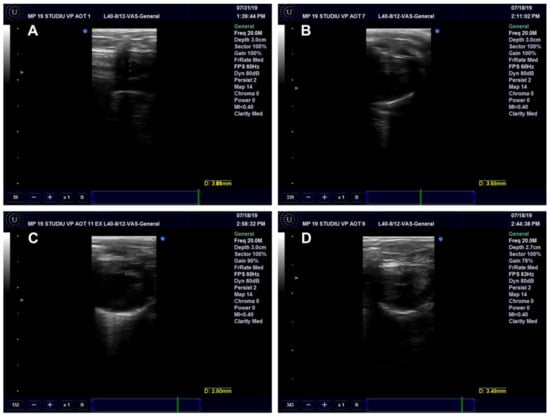

Ultrasound Examination of the Aorta and Left Ventricle